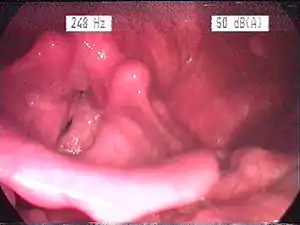

| Endoscopic image of an inflamed larynx caused by acid reflux | |

The larynx itself will often show erythema (reddening) and edema (swelling). This can be seen with laryngoscopy or stroboscopy (method depends on the type of laryngitis).[7]: 108 Stroboscopy may be relatively normal or may reveal asymmetry, aperiodicity, and reduced mucosal wave patterns.[16]

Other features of the laryngeal tissues may include

- Redness of the laryngeal tissues (acute)

- Dilated blood vessels (acute)

- Thick, yet dry laryngal tissue (chronic)

- Stiff vocal folds

- Sticky secretions between the vocal folds and nearby structures (the interarytenoid region)